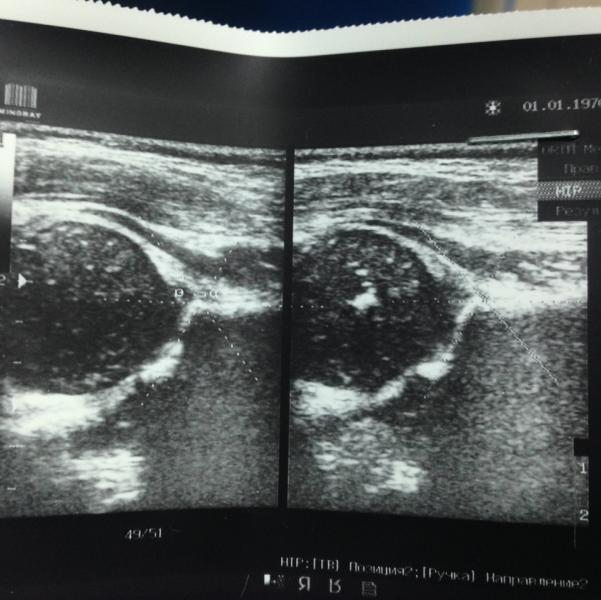

Сегодня были на УЗИ тазобедренного сустава и врач не обнаружила ядер окостенения правой стороны. У кого такое было??? Что делали, какой результат? Расскажите, что вам назначали и как детки потом начали ходить (а то нам сказали, что на ноги категорически не ставить, а он постоянно на ножки хочет опираться).??? Нам 3 месяца.

@shalkhaar, месяц назад мы были у ортопеда он нам сказал сделать УЗИ так как ножки у нас не раскладываются лягушкой, мы тогда сделали УЗИ тогда и правом и в левом не было ядер окостенения, ходили на парафин и массаж, повторно сегодня сделали УЗИ нет в правой